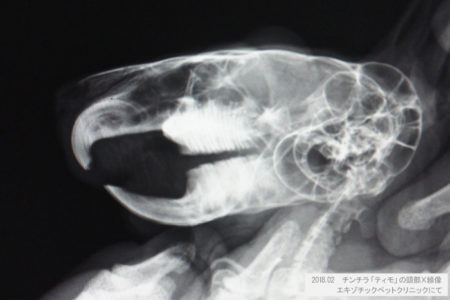

チンチラの健康診断としてよく行われている各種検査を追加するとどんな病気がわかるのだろう?28 December, 2018チンチラの健康管理22537 viewsチンチラの健康状態を評価するために、チンチラの健康診断としてどの程度お願いするかを決めるのは飼い主である私たち自身です。健康診断として行われている基本的な診察や、プラスしてよく...Read More